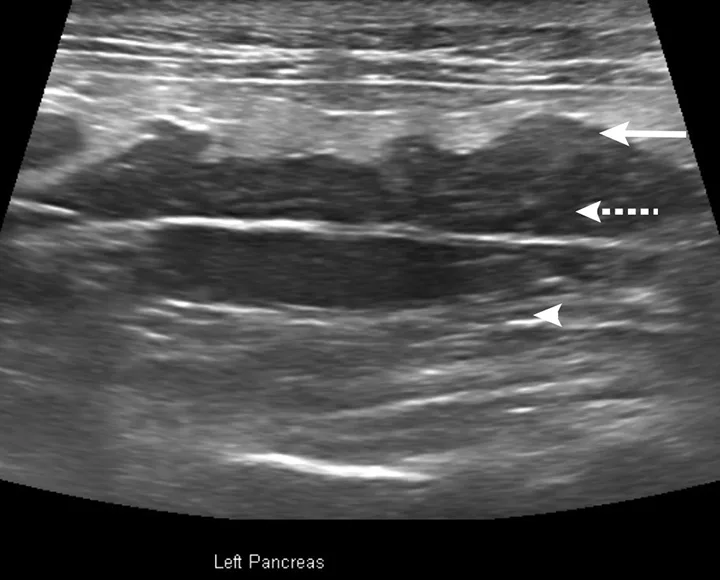

Abdominal ultrasonography is increasingly important for diagnosing pancreatitis via identification of pancreatic enlargement, changes in echogenicity, free fluid surrounding the pancreas, and hyperechogenicity of peripancreatic fat (Figures 1 and 2). Results of a study demonstrated good correlation with fPLI elevations.16

Ultrasound image of pancreas in a cat with arrows pointing to areas of interest.

FIGURE 1

Abdominal ultrasound of a cat with acute pancreatitis and triaditis. Hypoechogenicity of the pancreas (dashed arrow), hyperechoic mesentery (steatitis; arrowhead), and irregular, lobulated pancreatic margins (arrow) are visible.